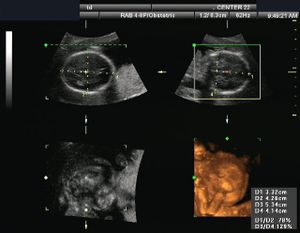

- متابعة وتصوير الجنين أثناء فترة الحمل.

| طب التوليد | Obstetrical sonography is commonly used during pregnancy to check on the development of the fetus. | انظر obstetric ultrasonography |

- ^ Dubose, T. J. (1985). "Foetal Biometry: Vertical Calvarial Diameter and Calvarial Volume". Journal of Diagnostic Medical Sonography. 1 (5): 205. doi:10.1177/875647938500100504.

- ^ "3D BPD Correction". July 2000. Retrieved 2008-09-27.